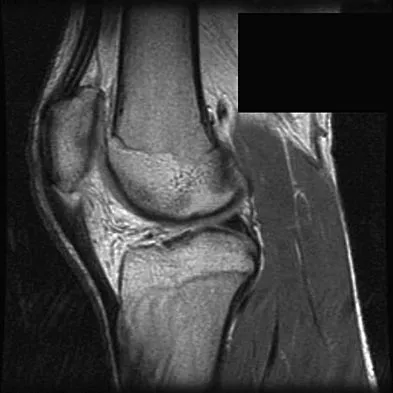

A 17-year-old basketball player and pole vaulter who has had anterior knee pain for the past 18 months now reports a recent inability to jump. Based on the MRI scan shown in Figure 11, management should consist of

Explanation